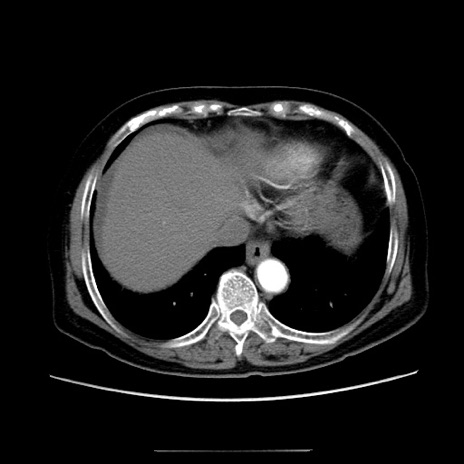

冠状断像

【症例】70歳代女性

【主訴】お腹が張る

【現病歴】1週間くらい前から腹部膨満の自覚あり。昨日夜から増悪したため、本日救急外来受診。

【身体所見】意識清明、BT 36.5℃、BP 165/106mmHg、HR 80bpm、SpO2 98%、腹部:膨満、軟、自発痛・圧痛なし、触診にて不快感あり、腸蠕動音:減弱

【データ】WBC 12600、CRP 1.04